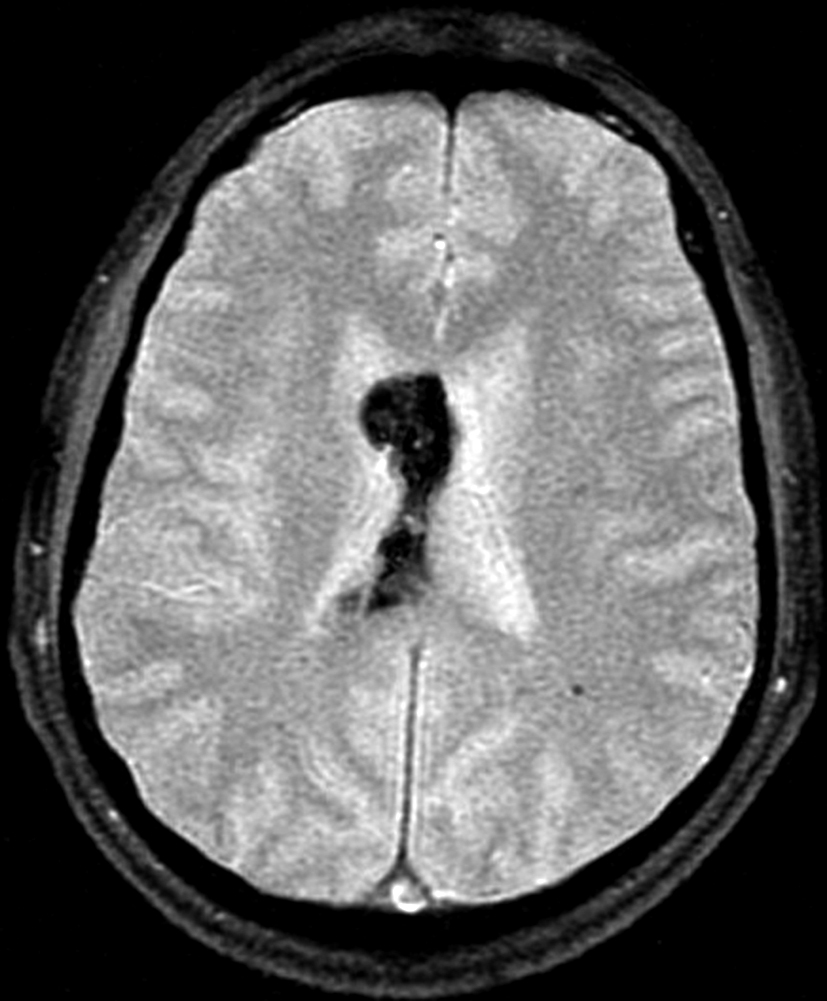

Con los hallazgos tomográficos, no se efectúan planteos diagnósticos y se realiza una resonancia magnética con la finalidad de obtener más datos semiológicos en busca de una aproximación diagnóstica. Se realizó el estudio por medio de secuencias T 1, FSE T 2, FLAIR, SWI y Difusión, en cortes axiales, FSE coronal y sagital T 1. Se realiza la administración de gadolinio DTPA en los tres planos. Se evidencia la lesión bien definida a nivel del ventrículo lateral derecho, que involucra al tronco del cuerpo calloso (Figura 2- C y 3- B). Presenta intensidad de señal heterogénea en secuencias T1 y T2 (Figura 3 y Figura 4). En secuencia ecogradiente se observa una señal marcadamente hipointensa y heterogénea, con un halo hipointenso bien definido (Figura 2- C). No presenta realce significativo tras la administración de Gadolinio (Figura 2- B) y en la secuencia de difusión no presenta restricción.

Figura 2 Resonancia magnética.

a) Imagen axial T1, lesión intraventricular con intensidad de señal heterogénea.

b) Tras la administración de Gadolinio no presenta realce significativo.

c) Imagen axial en secuencia ecogradiente donde se evidencia la lesión

hipointensa y heterogénea. Se observa la extensión de la lesión al cuerpo calloso.